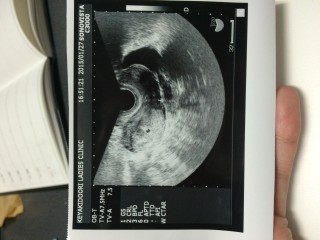

5週ですが既に22.6mmです!(大きい!) 先生からは9週くらいの大きさだね~気持ち大きめだね~ なんて言われましたが、順調のようで嬉しい!